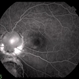

- RD, chorioretinal coloboma

- Scanning laser ophthalmoscope

- Color fundus photograph of a 43 year old male post retinal detachment surgery in a case of iridofundal coloboma.